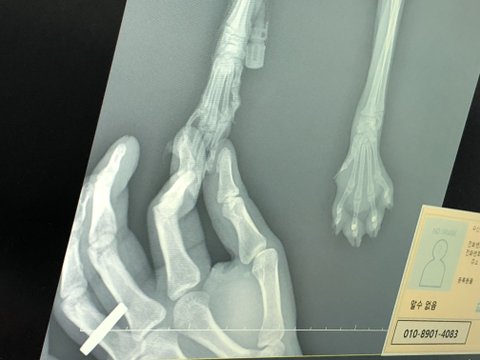

이대로 놔두면 아사로 죽을것 같아 구조 하였고 24시 병원에 데려가 간단한 검사를 했는데 한쪽 발 젤리가 어디에 박혀서 그게 염증이되어 고름이 무릎까지 올라와 왕발이 되었습니다. 모든걸 잘 이겨내고 행운을 누렸으면 해서 “행운이”라고 이름도 지었습니다.

오늘부터 갑자기 밥 안먹고 기운이 없어 병원에 가본바 검사에서 진드기 바이러스가 나왔습니다... 간수치 황달 빈혈등 제대러 된게 없습니다. 지금 겨우 수혈을 받은 상태이나 얼마나 수혈을 받아야 할지 기약이 없고, 언제 퇴원가능할지도 기약이 없습니다...

▪️4-5번 24시 용인 쓰담쓰담병원 응급으로 가서 발 감염 처치 및 드레싱

▪️9-10번 급 상태가 안좋아 서울에 있는 2차 병원 내원후 “진드기바이러스” 확인